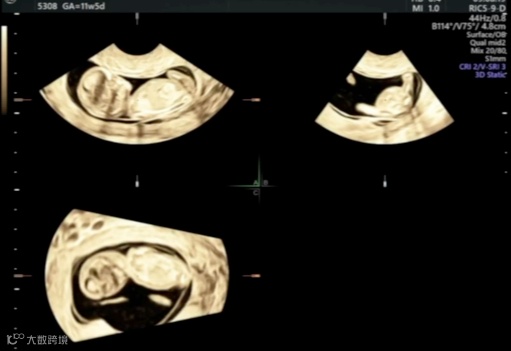

在超声机菜单上选取muti-plane、四幅画面,获得这张图。muti-plane多平面模式不同于render渲染模式,渲染模式下选择单幅画面只会显示3维图像,多平面模式就可以单独放大abc平面。

A平面是胎儿矢状切面,B平面是胎儿横切面,c平面是胎儿冠状切面。单纯旋转a切面很难获取标准正中矢状切面的,我们需要借助bc平面,只要bc平面标准了,a平面也自然是标准了。所以bc平面要选择能够快速识别是否标准的标志物,这里我选择了大脑镰,目标是b平面上大脑镰绝对垂直、c平面上大脑镰绝对平行,这样我们的a平面就是胎儿正中矢状切面了

适当放大图像,在a 平面移动观察点,让b平面容易辨认

在b平面移动观察点,让c平面容易辨认,注意b平面的观察点要放在大脑镰上,这样当b平面垂直后,才能在a平面上显示的是正中矢状切面。

在点选a平面情况下,旋转xy轴,让bc平面达到我们预期的位置,就可以看到a平面已经基本显示出正中矢状切面了。

微调后,我们在菜单内选择a平面-单幅图像,放大,就可以测量头臀长。

接着继续放大a平面,使胎儿头胸部占据整个画面,微调后显示NT的两条线,降低增益,完成NT测量就可以了。